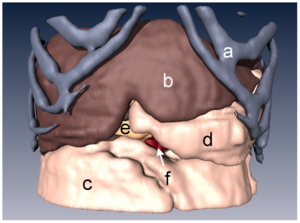

- 4.42 Retrosigmoid Implantation of an Active Bone Conduction Stimulator in a Patient with Chronic Otitis Media